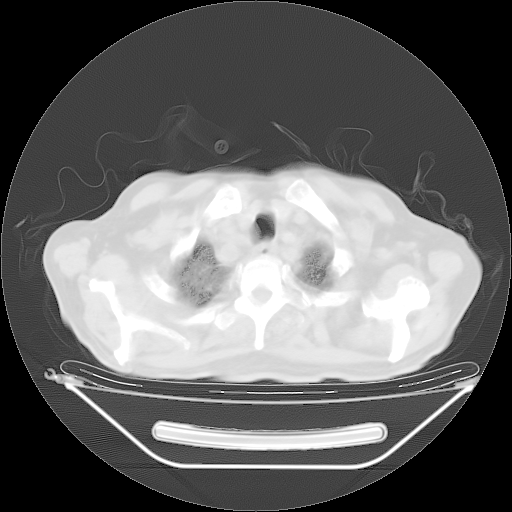

胸腹部CT,诊断意见:左上肺叶钙化灶、左侧胸膜局限性增厚并钙化、胆囊炎。描述部分肺组织呈磨玻璃样改变。